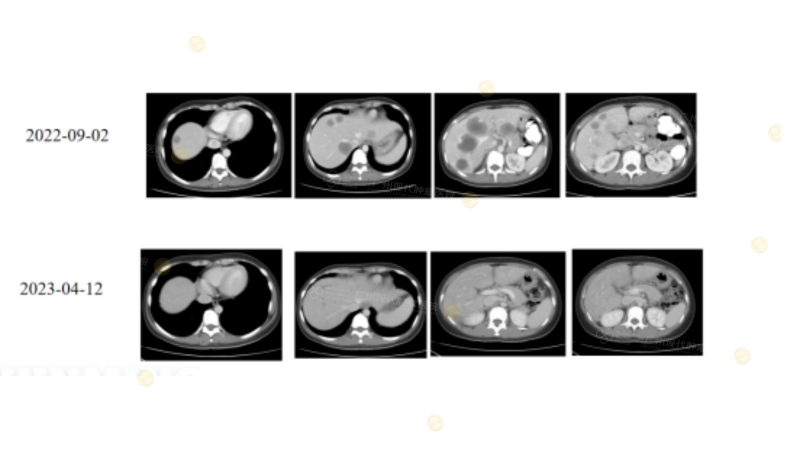

Case1

(注:25岁男性直肠癌肝转移,MSI-H/KRAS突变。PD-1生物治疗直肠原发灶CR,肝转移灶微波消融(MWA)局部干预,争取NED。)

Case2

(注:2019年直肠癌患者,生物治疗后肺转移病灶CR,后续出现新发肝脏转移灶,考虑患者存在继发耐药,给予行局部碘-125 粒子植入治疗,为患者争取NED。)

(注:30岁男性直肠癌术后肝多发转移(MSS/pMMR、NRAS G12D),多线生物治疗+靶向+局部治疗(Sintilimab+HAIC+Bevacizumab+MWA)后肝转移接近CR/NED,显示MSS CRLM患者可获突破性疗效。)